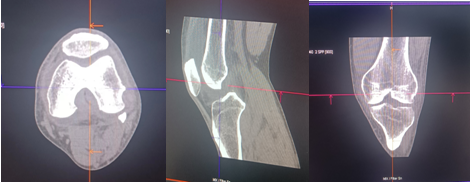

常规CT图像:对痛风石诊断没有特异性。

常规CT:显示骨质破坏及周围软组织高密度,不能特异性诊断。